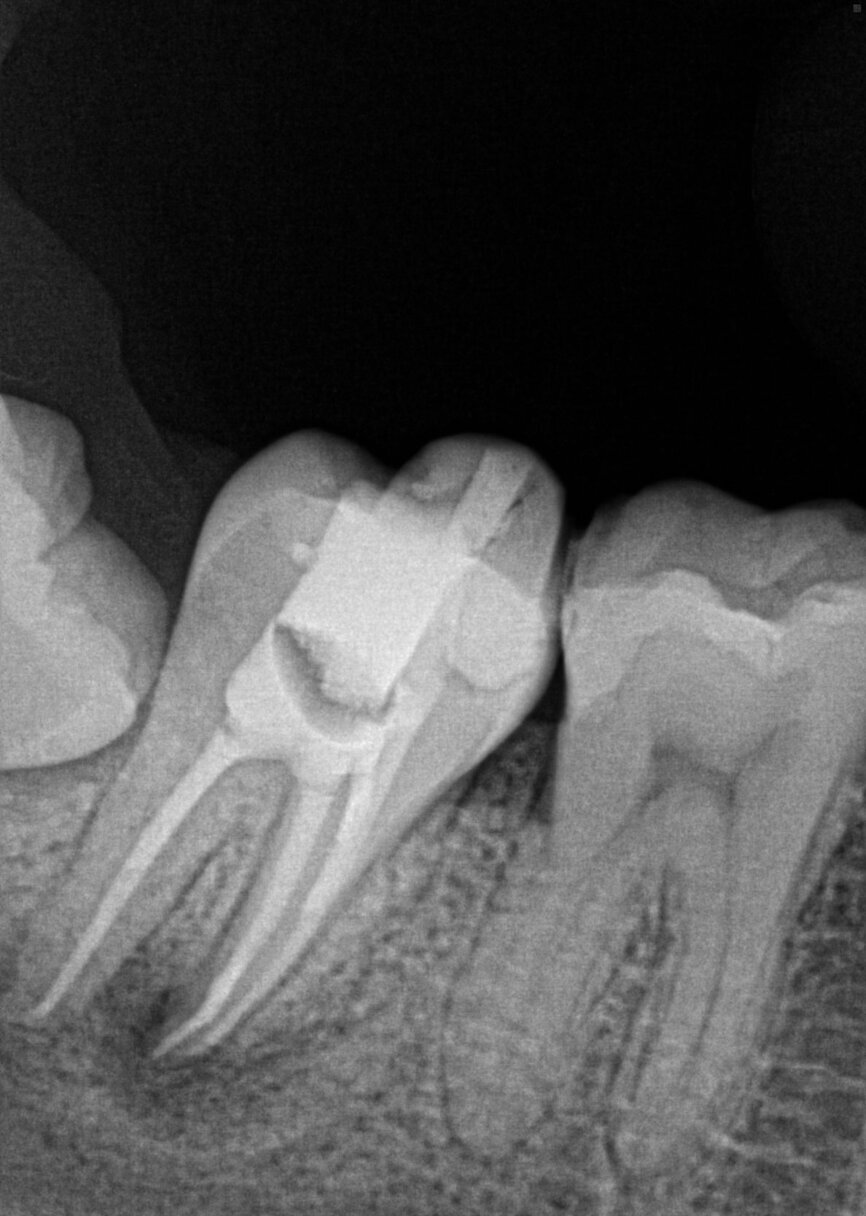

Fig. 17a: Case assisted with CBCT to determine anatomy pre-operatively. Note the multiple cross sections moving apically and the correlation to the 2-D view. Note also the conservative taper in relation to the root width. (Courtesy of Dr. Brett Gilbert)

Fig. 17b: Case assisted with CBCT to determine anatomy pre-operatively. Note the multiple cross sections moving apically and the correlation to the 2-D view. Note also the conservative taper in relation to the root width. (Courtesy of Dr. Brett Gilbert)

Fig. 17c: Case assisted with CBCT to determine anatomy pre-operatively. Note the multiple cross sections moving apically and the correlation to the 2-D view. Note also the conservative taper in relation to the root width. (Courtesy of Dr. Brett Gilbert)

Fig. 17d: Case assisted with CBCT to determine anatomy pre-operatively. Note the multiple cross sections moving apically and the correlation to the 2-D view. Note also the conservative taper in relation to the root width. (Courtesy of Dr. Brett Gilbert)

Fig. 17e: Case assisted with CBCT to determine anatomy pre-operatively. Note the multiple cross sections moving apically and the correlation to the 2-D view. Note also the conservative taper in relation to the root width. (Courtesy of Dr. Brett Gilbert)

Fig. 17f: Case assisted with CBCT to determine anatomy pre-operatively. Note the multiple cross sections moving apically and the correlation to the 2-D view. Note also the conservative taper in relation to the root width. (Courtesy of Dr. Brett Gilbert)

Managing complex anatomy is much simpler if the clinician has a pre-operative road map. The CBCT provides the roadmap and the surgical microscope the lens (literally) through which to visualize the result. Aside from a relaxed patient who is profoundly numb, being able to visualize anatomy by taking a pre-operative (and possibly intra-operative) CBCT and using a surgical microscope during treatment have no substitutes. They are the current “Gold Standard” in that 3-D imaging shows the clinician the true reality of a clinical situation as opposed to the suggestion gained from a 2-D radiograph. Proper interpretation of imaging prior to and/or during endodontic treatment goes a long way in taking the “guesswork” out of identifying canal location and other anatomical complexities as the procedure unfolds. In a 2014 study by El Fayad and Johnson, it was determined that when having a pre-operative CBCT as compared to 2-D radiographs alone, the treatment plan was modified 62 percent of the time. This is a huge game changer to think that the information learned from 3-D imaging changed the plan of treatment over six times out of 10 (Fig. 4).[2]